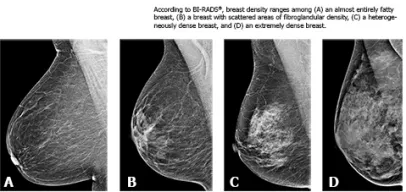

The breast density is one of the greatest risk factors for breast cancer, women with high density breasts (density more than 75 percent) have between four to six times more risk than women with a MD of less25 percent.